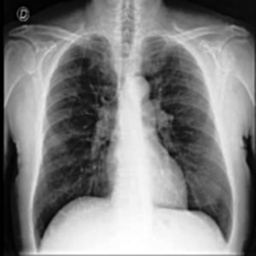

These steps collectively enhance the critical features of the CXR images, aiding in more accurate analysis. Figure2 shows the comparison between CXR images before and after preprocessing highlighting the enhanced clarity and feature extraction achieved through the applied filters.

(a) Before Preprocessing

(b) After Preprocessing

Figure 2: Comparison of CXR Images Before and After Preprocessing